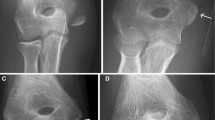

Standard orthopedic treatment is to use non-degradable metal implants to fixate the fracture site. This kind of treatment not only causes rejection and stress shielding, but also requires a second surgery to remove the metal implants. In addition, this kind of treatment increases physical pain and is a serious financial burden to patients. However, biodegradable implants do not require a second surgery for removal and have good biocompatibility and osteoconductivity.

Biodegradable implants do not require a second surgery for removal and have good biocompatibility and osteoconductivity. Consequently, they are an ideal treatment and are increasingly used for orthopedic surgical patients. The most common indications for biodegradable implants include craniofacial reconstruction, anterior cruciate ligament reconstruction, meniscus repair, ankle fracture treatment, and tibia and fibula fracture treatment.